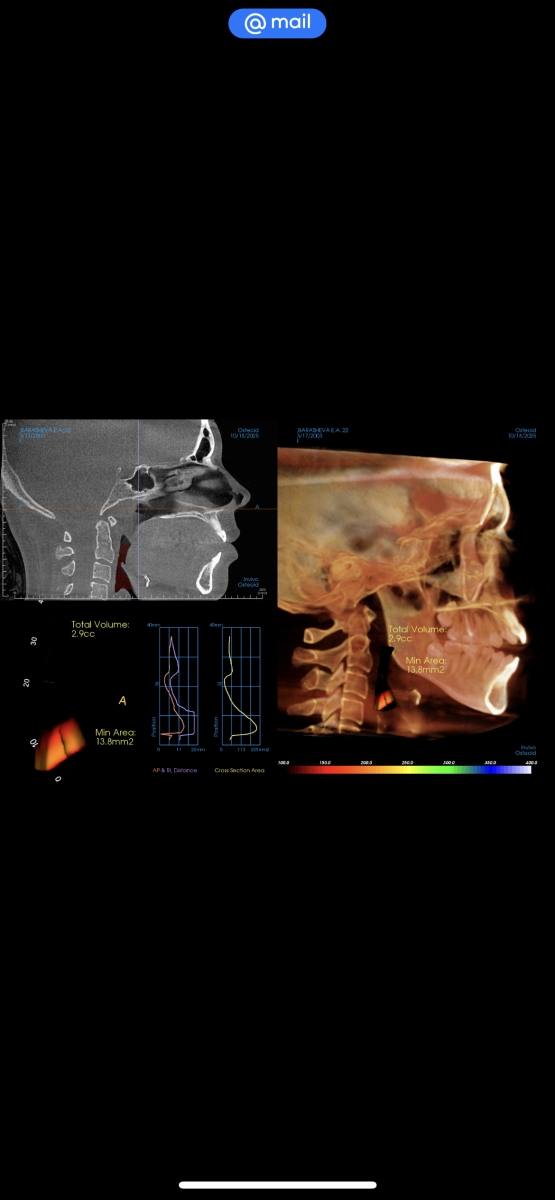

У меня открытый прикус, в детской стоматологии мне сказали делать только операцию

Сейчас уже прохожу во взрослой клинике обследование и тоже самое говорят, брекеты при открытом прикусе не помогут только члх